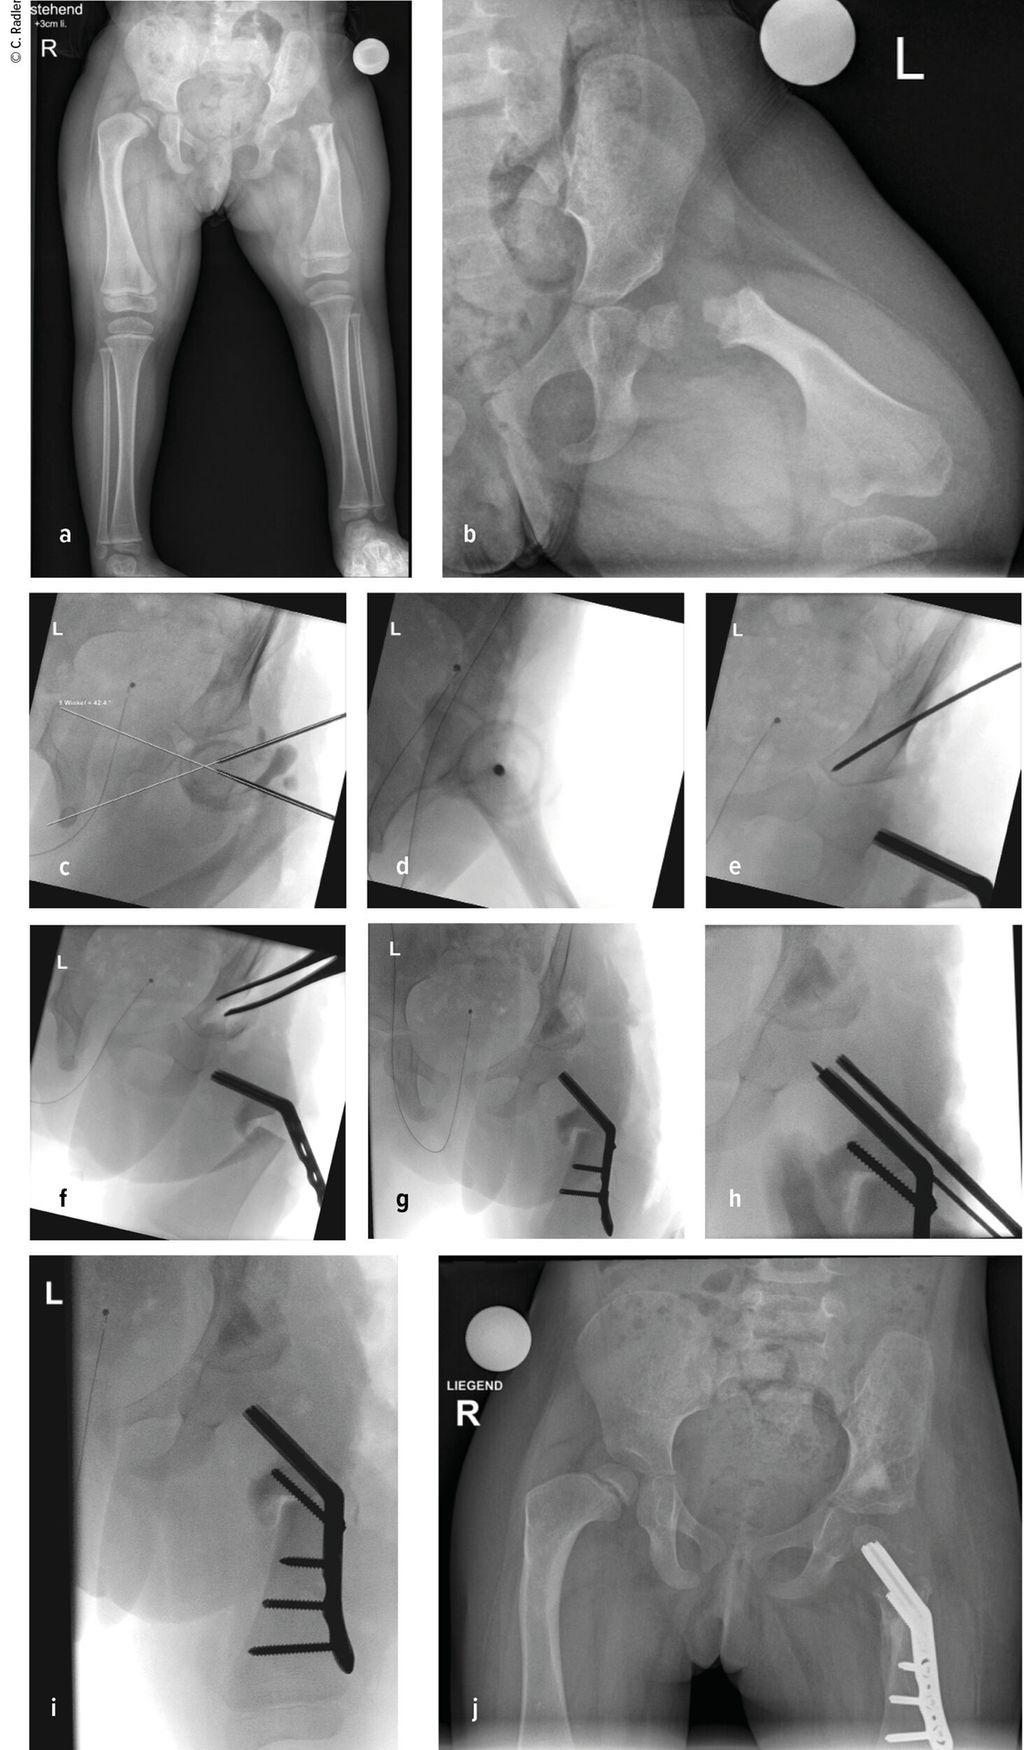

Im Rahmen dieser Operation können auch die Retrotorsion und der Schenkelhalsvarus korrigiert werden. Eine Verlängerung bei nicht optimal überdachter Hüfte führt meist zu einer Subluxation oder Luxation, was eine schwerwiegende Komplikation darstellt, die nur schwer und meist nicht folgenlos zu beheben ist. Auch bei älteren Patienten ist die Überdachung vor einer eventuellen Verlängerung zu überprüfen, wobei besonders ab dem 4. Lebensjahr eine Tripelosteotomie eine bessere Überdachung und Einstellung der Pfanne gegenüber einer Acetabuloplastik erlaubt (Abb.2).

Abb. 2:Versorgung eines kurzen Pfannendachs mittels Tripelosteotomie, um die Hüfte während der Verlängerung vor (Sub-)Luxation zu schützen